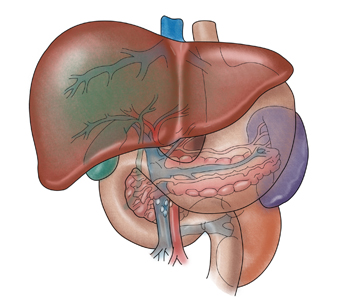

간이식은 환자분이 급성 혹은 만성 간부전으로 진단되어

생명유지에 필수적인 간의 기능을 상실한 경우나,

간에 발생한 종양 (간세포암, 간내 거대 혈관종, 다발성 간낭종 등) 에 대해

절제수술로 치유가 어려울 때, 그 적응증이 될 수 있습니다.

만성간부전은 다양한 원인에 의해 발생할 수 있는데,

처음에 정상이었던 간이 급, 만성간염을 앓으면서

간이 딱딱해지는 간경변증으로 진행되는 경우,

정상적으로 기능을 하는 간세포가 감소되고 간문맥압이 상승하게 됩니다.

그 결과 간에서의 독성물질 해독 기능의 감소로 인한 증상과

간문맥을 통해 복강내 정맥혈류가 심장으로 유입되는 정상적인 혈류순환에 장애가 발생하게 됩니다.

환자가 만약 복수 및 그로 인한 복막염, 토혈, 혈변, 간성혼수, 황달, 간신증후군 등의 주요한 증상을 보인다면,

최상의 치료법인 간이식을 중요한 치료 방법 중의 하나로 고려해야 합니다.